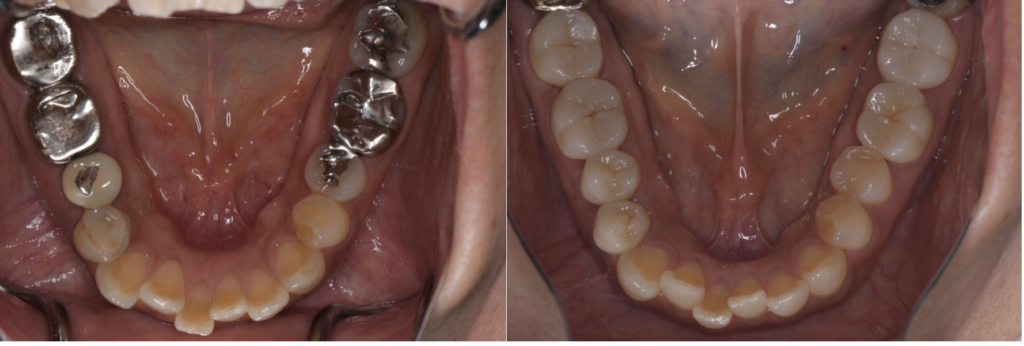

全顎治療

全顎治療(フルマウス治療)では、歯の健康だけではなく、見た目の美しさも重視しております。

詳しく見る